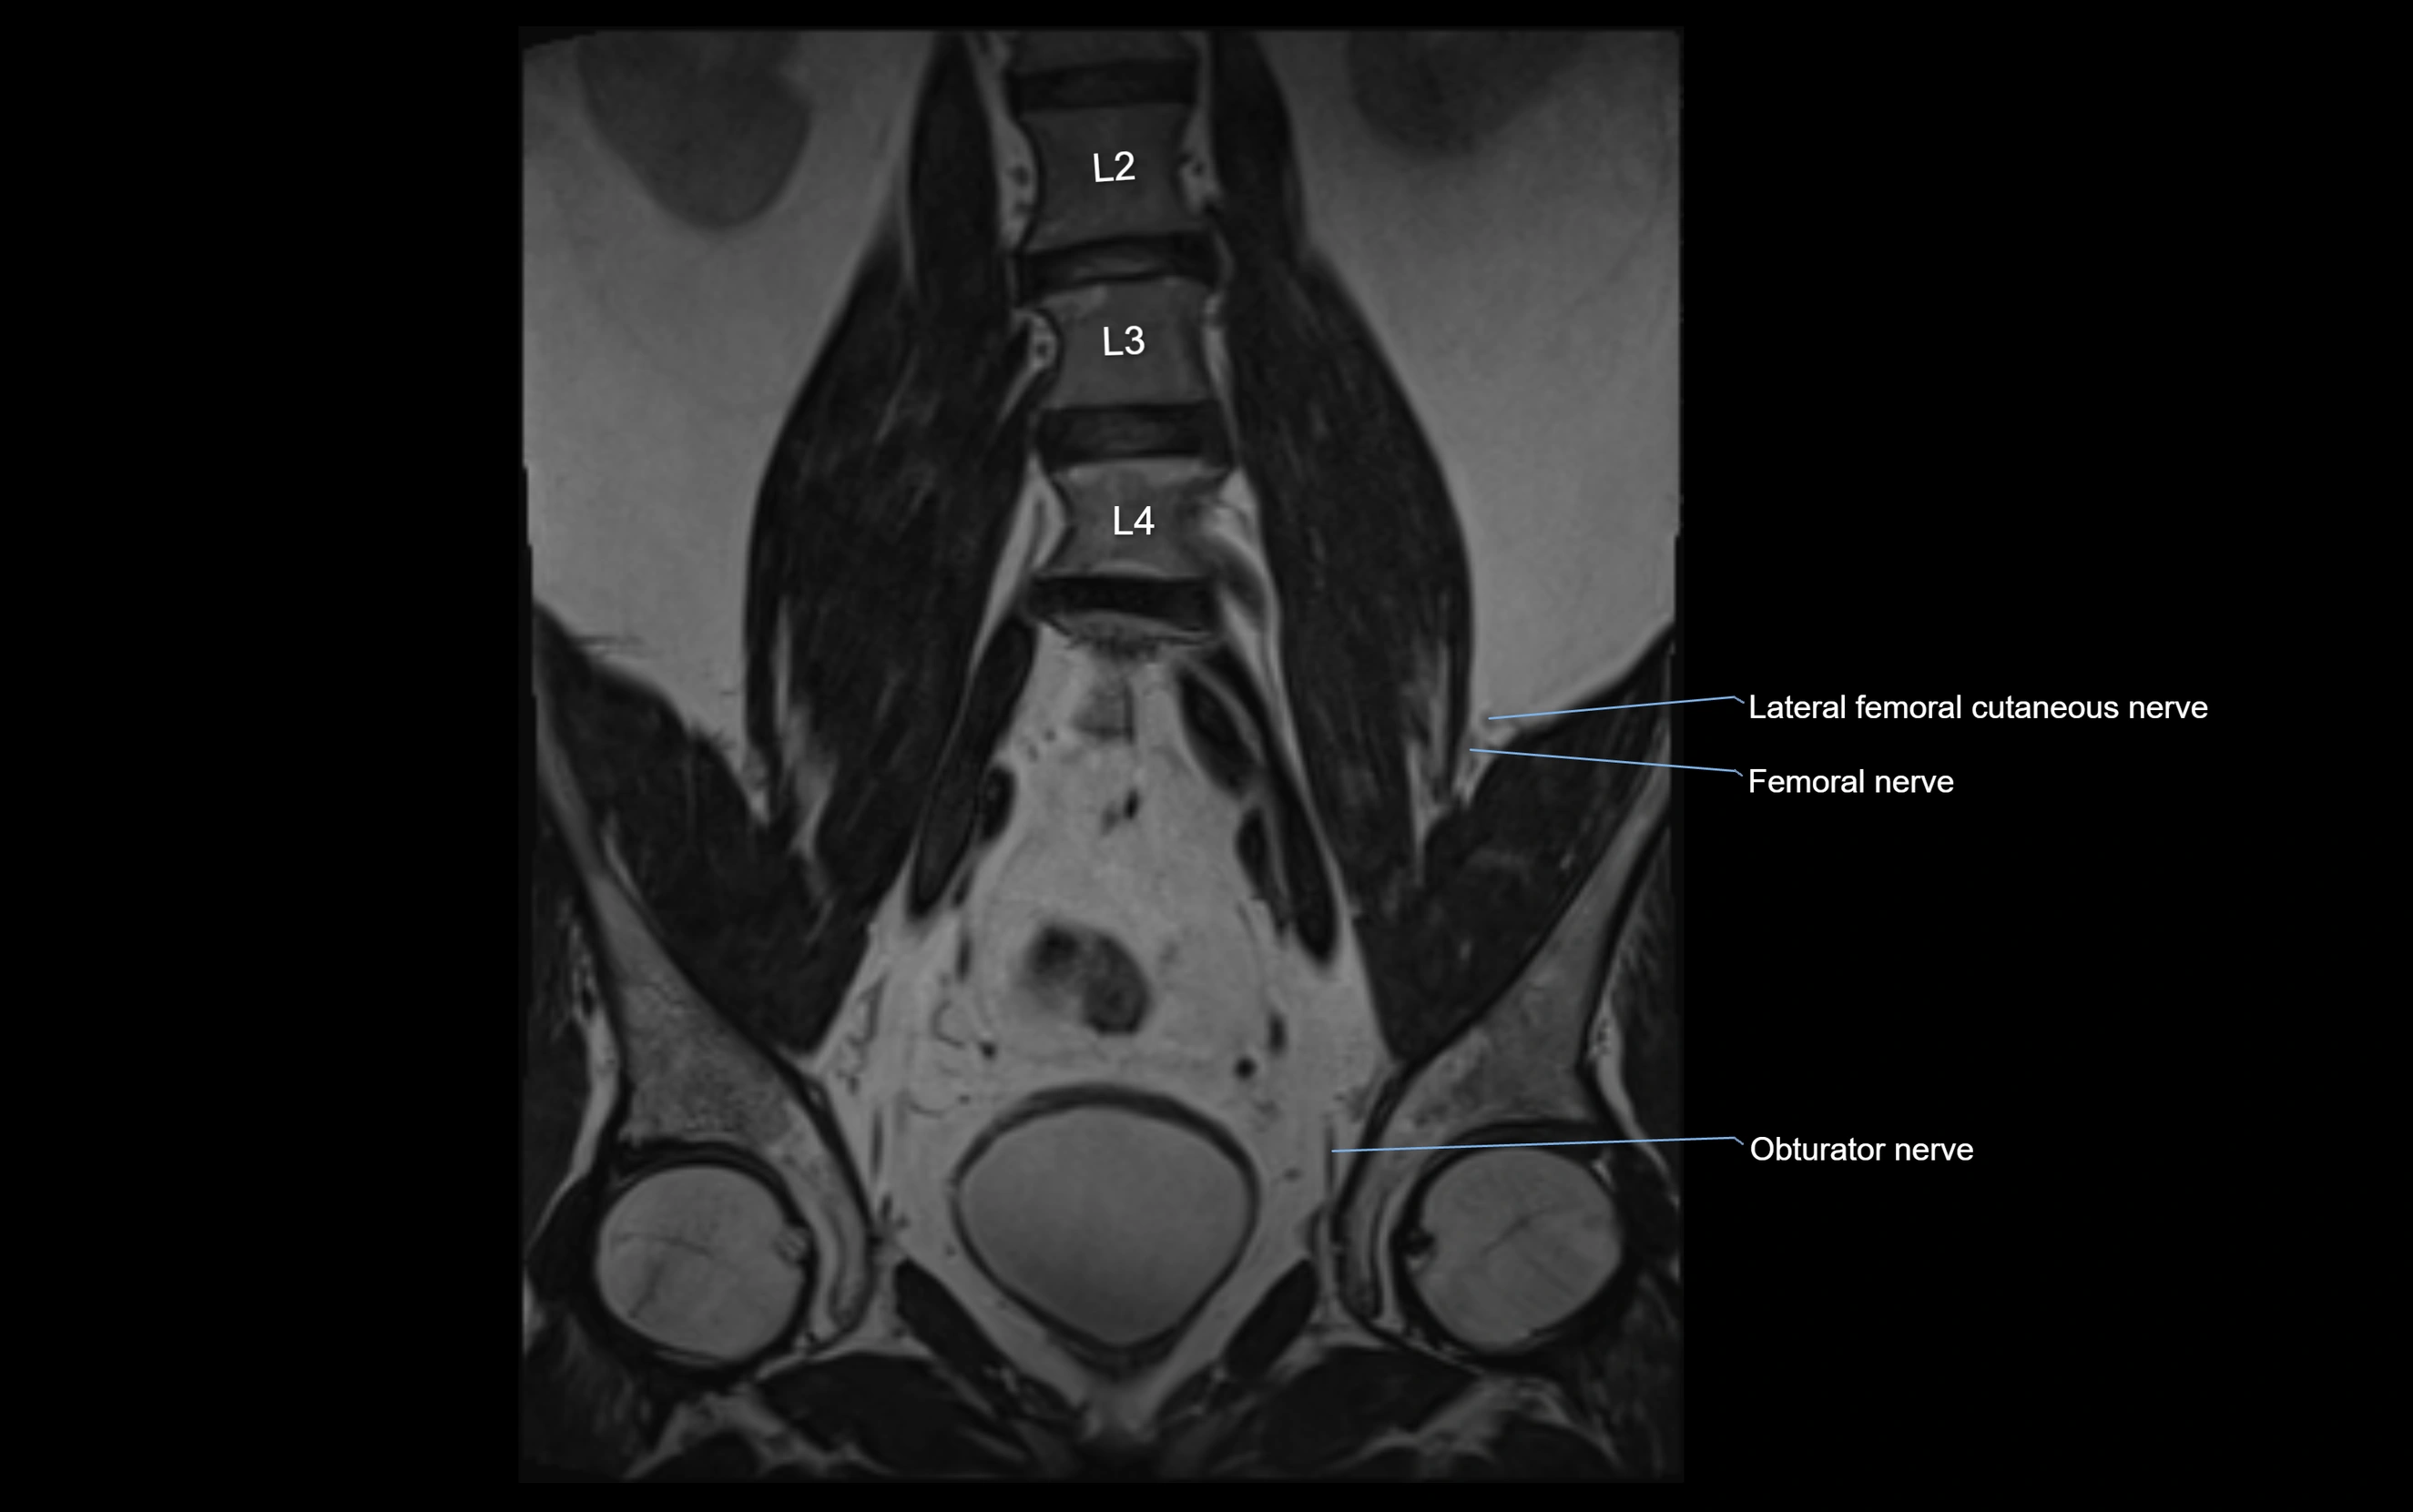

MRI Appearance

T1-weighted images:

• Nerve appears as a very thin low-to-intermediate signal intensity structure

• Surrounded by bright fat, aiding visualization

T2-weighted images:

• Nerve shows intermediate to mildly hyperintense signal compared to muscle

• Pathological involvement appears brighter

STIR (Short Tau Inversion Recovery):

• Normal nerve appears dark

• Inflamed or entrapped nerve appears bright hyperintense

T1 Fat-Sat Post-Contrast:

• Normal nerve enhances minimally

• Pathologic nerve (neuritis, entrapment, tumor infiltration) shows focal or diffuse enhancement

3D T2 SPACE / CISS:

• Nerve appears intermediate to mildly hyperintense compared to muscle

• Surrounded by bright fat or CSF, improving visualization

• Best sequence for mapping small pelvic nerves such as the anococcygeal